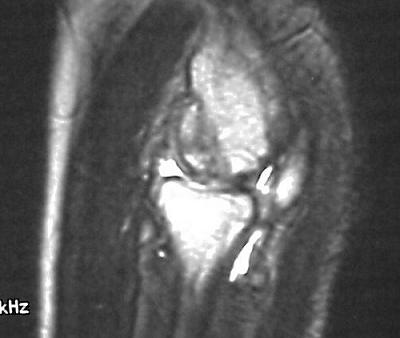

MRI shows an osteochondral sequestrum of the anterior capitellum:

Five years later, he has limited motion (E/F 35/100) and painful clicking with elbow flexion and extension.

Plain films show humeral osteophytes and posttraumatic changes of the capitellum and radial head.